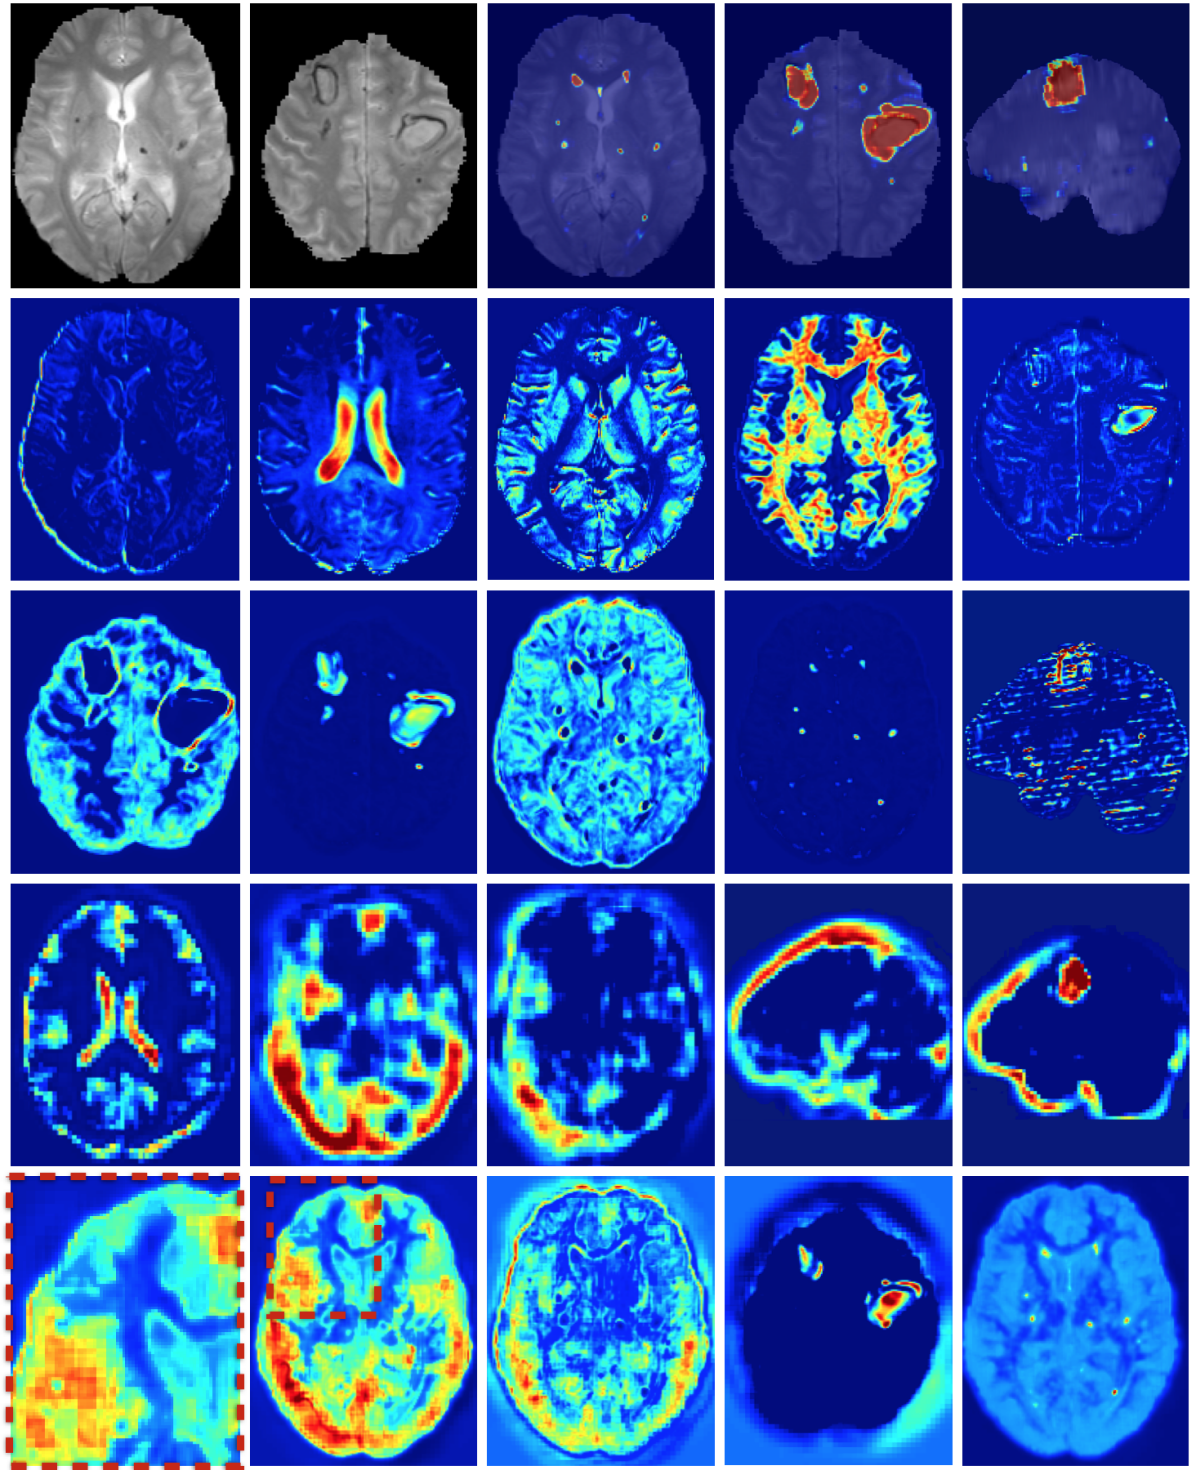

The discriminative power of the learned features is indicated by the success of recent CNN-based systems in matching human performance in domains where it was previously considered too ambitious (He et al. (2015); Silver et al. (2016)). Analysis of the automatically extracted information could potentially provide novel insights and facilitate research on pathologies for which little prior knowledge is currently available. In an attempt to illustrate this, we explore what patterns have been learned automatically for the lesion segmentation tasks. We visualize the activations of DeepMedic’s FMs when processing a subject from our TBI database. Many appearing patterns are difficult to interpret, especially in deeper layers. In Fig. 14 we provide some examples that have an intuitive explanation. One of the most interesting findings is that the network learns to identify the ventricles, CSF, white and gray matter. This reveals that differentiation of tissue type is beneficial for lesion segmentation. This is in line with findings in the literature, where segmentation performance of traditional classifiers was significantly improved by incorporation of tissue priors (Van Leemput et al. (1999); Zikic et al. (2012)). It is intuitive that different types of lesions affect different parts of the brain depending on the underlying mechanisms of the pathology. A rigorous analysis of spatial cues extracted by the network may reveal correlations that are not well defined yet.

Similarly intriguing is the information extracted in the low-resolution pathway. As they process greater context, these neurons gain additional localization capabilities. The activations of certain FMs form fields in the surrounding areas of the brain. These patterns are preserved in the deepest hidden layers, which indicates they are beneficial for the final segmentation (see two last rows of Fig. 14). We believe these cues provide a spatial bias to the system, for instance that large TBI contusions tend to occur towards the front and sides of the brain (see Fig. 1(c)). Furthermore, the interaction of the multi-resolution features can be observed in FMs of the hidden layer that follows the concatenation of the pathways. The network learns to weight the output of the two pathways, preserving low resolution in certain parts and show fine details in others (bottom row of Fig. 14, first three FMs). Our assumption is that the low-resolution pathway provides a rough localization of large pathologies and brain areas that are challenging to segment, which reserves the rest of the network’s capacity for learning detailed patterns associated with the detection of smaller lesions, fine structures and ambiguous areas.